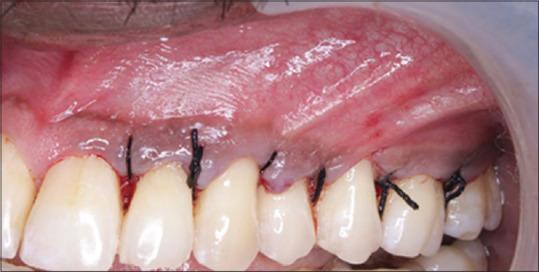

使用黏膜移植术治疗附着龈宽度不足

Management of inadequate width of attached gingiva using mucograft.

Attached gingiva around the teeth is crucial in preserving periodontal health. Plaque development and soft-tissue recession are both prevented by adequate attached gingiva. The processes for harvesting soft-tissue grafts are frequently accompanied by some level of morbidity which results in commercially available xenogeneic collagen matrices. The blood clot is more effectively stabilized by this collagen matrix, which also promotes vascularization. Furthermore, this biomaterial enhances root coverage and keratinized gingiva regeneration in both width and thickness. The purpose of the case report is to increase the width of attached gingiva using Mucograft. This case report highlights a case scenario where a patient presented with probing depth of 6-8 mm in relation to 24, 25, 26, 27, and 28, Grade I mobility in relation to 25.26, and 1 mm of the width of attached gingiva in relation to 25, 26, and 27. Flap surgery was done and simultaneously vestibular deepening was done in relation to 25, 26, and 27, and mucograft was placed and stabilized. On a 3-month follow-up, probing pocket depth was 3 mm and 4 mm of width of the attached gingiva was seen in 25, 26, and 27. The Mucograft was beneficial in this clinical case for the purpose of extending the width of the associated gingiva, making it a feasible treatment option for soft-tissue augmentation.

牙齿周围的附着龈对于保持牙周健康至关重要。充足的附着龈可预防菌斑形成和软组织退缩。获取软组织移植物的过程常常伴随着一定程度的发病率,这导致了市售的异种胶原基质的出现。这种胶原基质能更有效地稳定血凝块,还能促进血管化。此外,这种生物材料可增强牙根覆盖以及角化龈在宽度和厚度上的再生。该病例报告的目的是使用Mucograft增加附着龈的宽度。本病例报告突出了这样一个病例情况:一名患者24、25、26、27和28号牙的探诊深度为6 - 8毫米,25、26号牙为I度松动,25、26和27号牙的附着龈宽度为1毫米。进行了翻瓣手术,同时对25、26和27号牙进行了前庭加深,并放置并固定了Mucograft。在3个月的随访中,25、26和27号牙的探诊袋深度为3毫米,附着龈宽度为4毫米。在这个临床病例中,Mucograft对于增加相关牙龈的宽度是有益的,使其成为软组织增量的一种可行治疗选择。